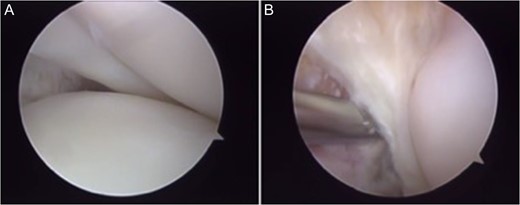

The patient underwent arthroscopic ACL reconstruction using ipsilateral flexor tendons as graft, PCL reconstruction using contralateral flexor tendons as graft and partial meniscectomy (Figs 3–5).

Arthroscopy surgery view during cruciate ligaments reconstruction. Note in (A) and (B) the ligaments absence. The lateral meniscus has not its bone tibial insertion of the posterior horn (*), which continued with the anterior meniscus femoral ligament (Humphry), which was hypertrophied (**). LFC, lateral femoral condyle.

Another interesting detail noted in this case was the absence of the tibial bone insertion of the posterior horn of the lateral meniscus, which in this case was continued with a hypertrophied meniscal femoral ligament (Fig. 3). Perhaps an anatomical attempt to stabilize the knee, but without success.